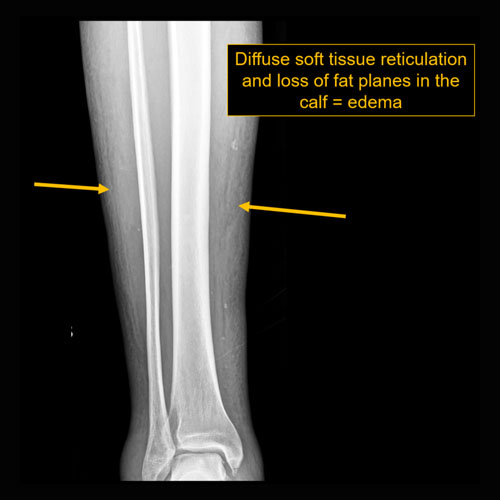

There is soft tissue reticulation, fullness, or obscuration of normal fat planes. |

Yes | NA |

Mild soft tissue edema along the proximal lateral calf. No radiographic evidence for underlying acute osseous abnormality.